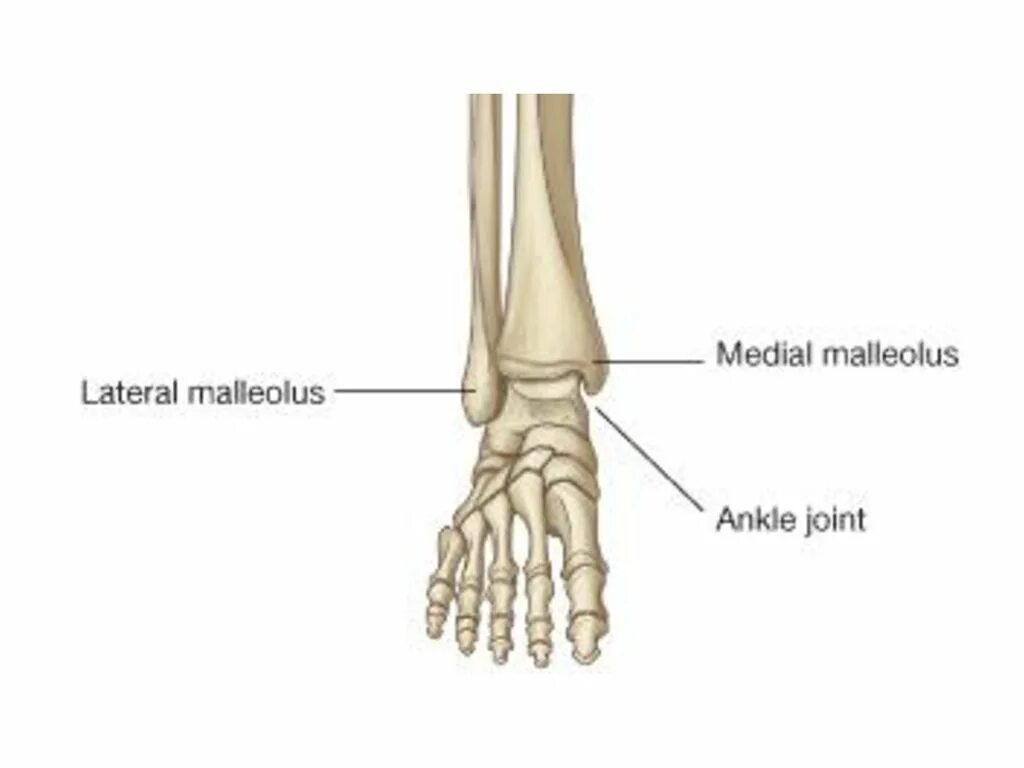

Латеральная лодыжка латынь